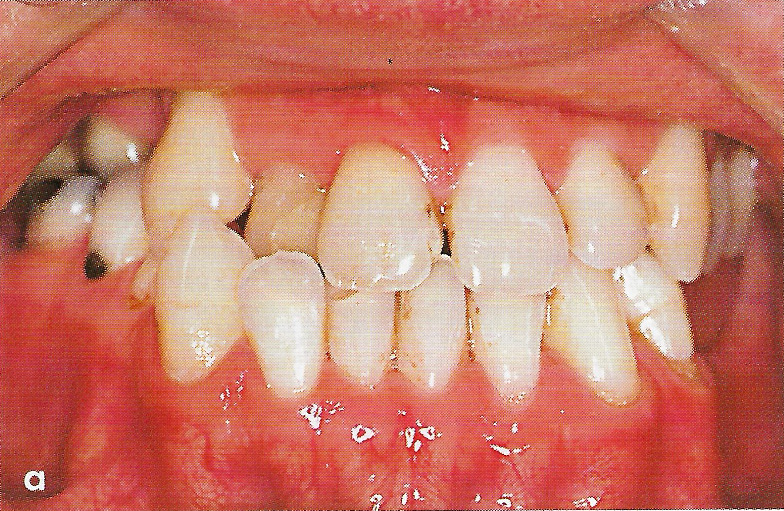

Abb. 1 a bis h Extra- und intraorale Ansicht der Patientin vor Behandlungsbeginn: Kopfbiß beziehungsweise umgekehrter Schneidezahnüberbiß und beidseitiger Kreuzbiß als Folge einer maxillären Hypoplasie sowie hälftenungleicher Mesialbiß infolge mandibulärer Verschiebung nach rechts.

Diese Patientin war zu Behandlungsbeginn 7 Jahre alt. Sie hatte einen hälftenungleichen Mesialbiß infolge mandibulärer Verschiebung mit Kopfbiß beziehungsweise umgekehrter inzisaler Stufe, rechtsseitigem vollem Kreuzbiß und linksseitigem doppeltem Höckerbiß, maxillärer Kompression sowie Platzmangel in beiden Kiefern (Abb. 1 a bis h). Die kephalometrische Analyse ergab eine progene Kieferlagebeziehung, bedingt durch eine unterentwickelte Maxilla bei vertikalem Gesichtsschädelaufbau.

Die Patientin wies nach der 8 ½ monatigen Protraktionstherapie eine positive inzisale Stufe auf, der Kreuzbiß und der Mesialbiß waren korrigiert; Zahnkippungen waren nicht erkennbar (Abb. 12 a bis h).